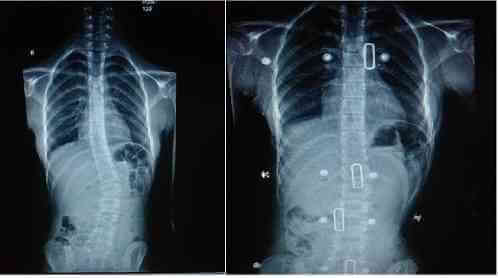

Omurga Deformitesi İçin Korse Tedavisi

İskelet gelişimini tamamlamamış hastalarda açısı 10-40 derece olan çocuklarda biyomekanik tasarımı doğru olan skolyoz korsesi ile başarılı sonuçlar alınır. Korseler, aktif iskelet büyümesi esnasında eğriliğin artmasını engellemek için karşı destek olarak görev yapar.Eğriliği 10-40 derece arasında olan ve büyüme potansiyeli olan kişilerde etkili olan bir yöntemdir

Başarı korsenin dizaynı kadar takip ve çocuğun belirlenen sürelerde korseyi giymesine bağlıdır. Piyasada birçok çeşit korse vardır. Hepsi çocuk büyürken eğriliğinin artmasını engellemek için dizayn edilmiştir. Ancak uygulayıcı teknikerin bilgi ve deneyimi çok büyük önem taşır. Ayrıca uygulanan korsenin hekim tarafından tekrar kontrolü ve gerekli düzeltmeler varsa yapılması gerekecektir. Deneyimsiz ve kalitesiz üretimlerin hem kullanıcı için hem de korse uygulamalarının etkinliğine ilişkin olumsuz sonuçlara neden olacağı unutulmamalıdır.

ABD ve Kanada’da çok merkezli olarak yürütülen ve erken dönem sonuçları 2013’te yayınlanan bir çalışma, korse kullanan hastaların ameliyat olma oranlarının, kullanmayanlara göre daha düşük olduğunu açıkça göstermiştir. Yani korse kullananların ameliyat olma ihtimali düşmektedir. Bu erken sonuçla çalışma durdurulmuş ve bütün hastalara korse verilmesi kararlaştırılmıştır.

Korsenin günde 20-23 saat takılı kalması etki gösterme açısından önemli bulunmuştur. NESA ORTOPEDİ olarak bünyemizde korse uyguladığımız bir çok hastamızın skolyoz derecesi sabit kalmış yada azalmıştır. Bu sayede bir çok hasta ameliyat olmaktan kurtulmuşlardır.